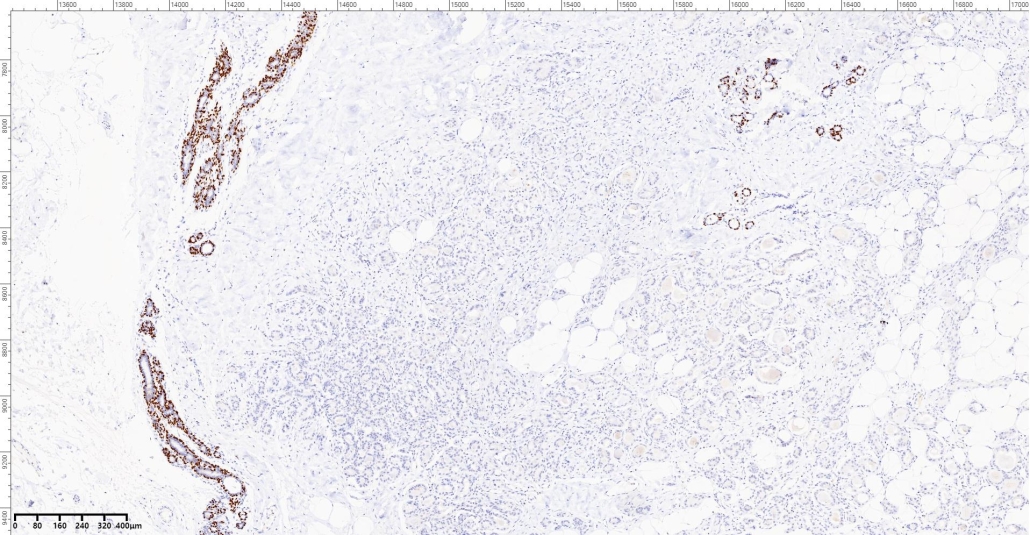

A 46-year-old woman presents with a slowly enlarging, non-tender palpable lump in the upper outer quadrant of the breast. Mammography shows an ill-defined density without calcifications. Local excision is performed.